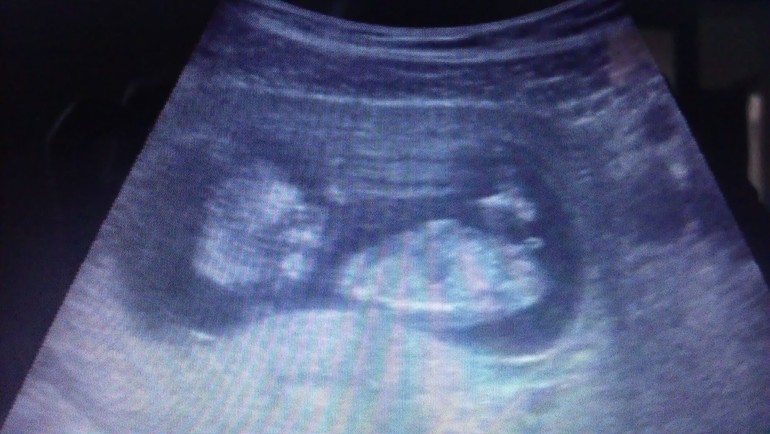

В общем делала УЗИ и по животу, и внутреннее, муж как-то почти без эмоций наблюдал, наверное был под впечатлением) УЗИ и 3Д, и 4Д, прям она говорит как в реальном измерении, полупрозрачное все.

КТР-56мм, БПР-14мм, ОЖ-55мм, ДБ-7мм, толщина воротникового пространства 1,71мм, ЧСС 161 уд. в мин. Там еще много чего написано, много переписывать)) в общем слава Богу все хорошо и соответствует ровно акушерскому сроку.